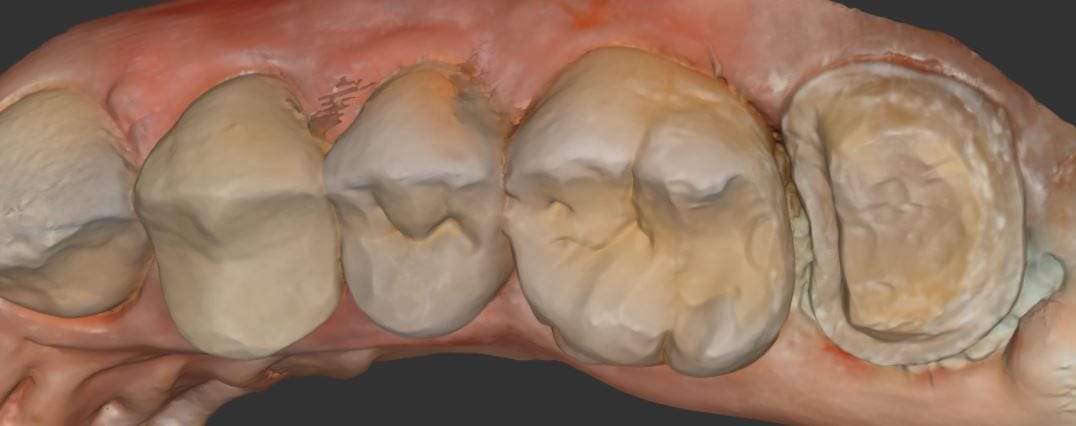

It was a long struggle to find margins with the Omnicam and after 4 years it was sold. The margin definition and resolution never reached an acceptable level. After seeing margins from high resolution scans by the Medit and defining them in exocad, it completely validated that we shouldn’t settle for anything less than the highest standard. This is an scan performed on a upper second molar with tough access, replacing a failing crown.